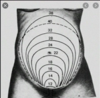

Determine a altura uterina de acordo com as semanas de gestação listadas abaixo:

- 12 semanas:

- 16 semanas:

- 20 semanas:

Altura uterina

- 12 semanas: na sínfise púbica

- 16 semanas: entre sínfise e umbigo

- 20 semanas: na cicatriz umbilical